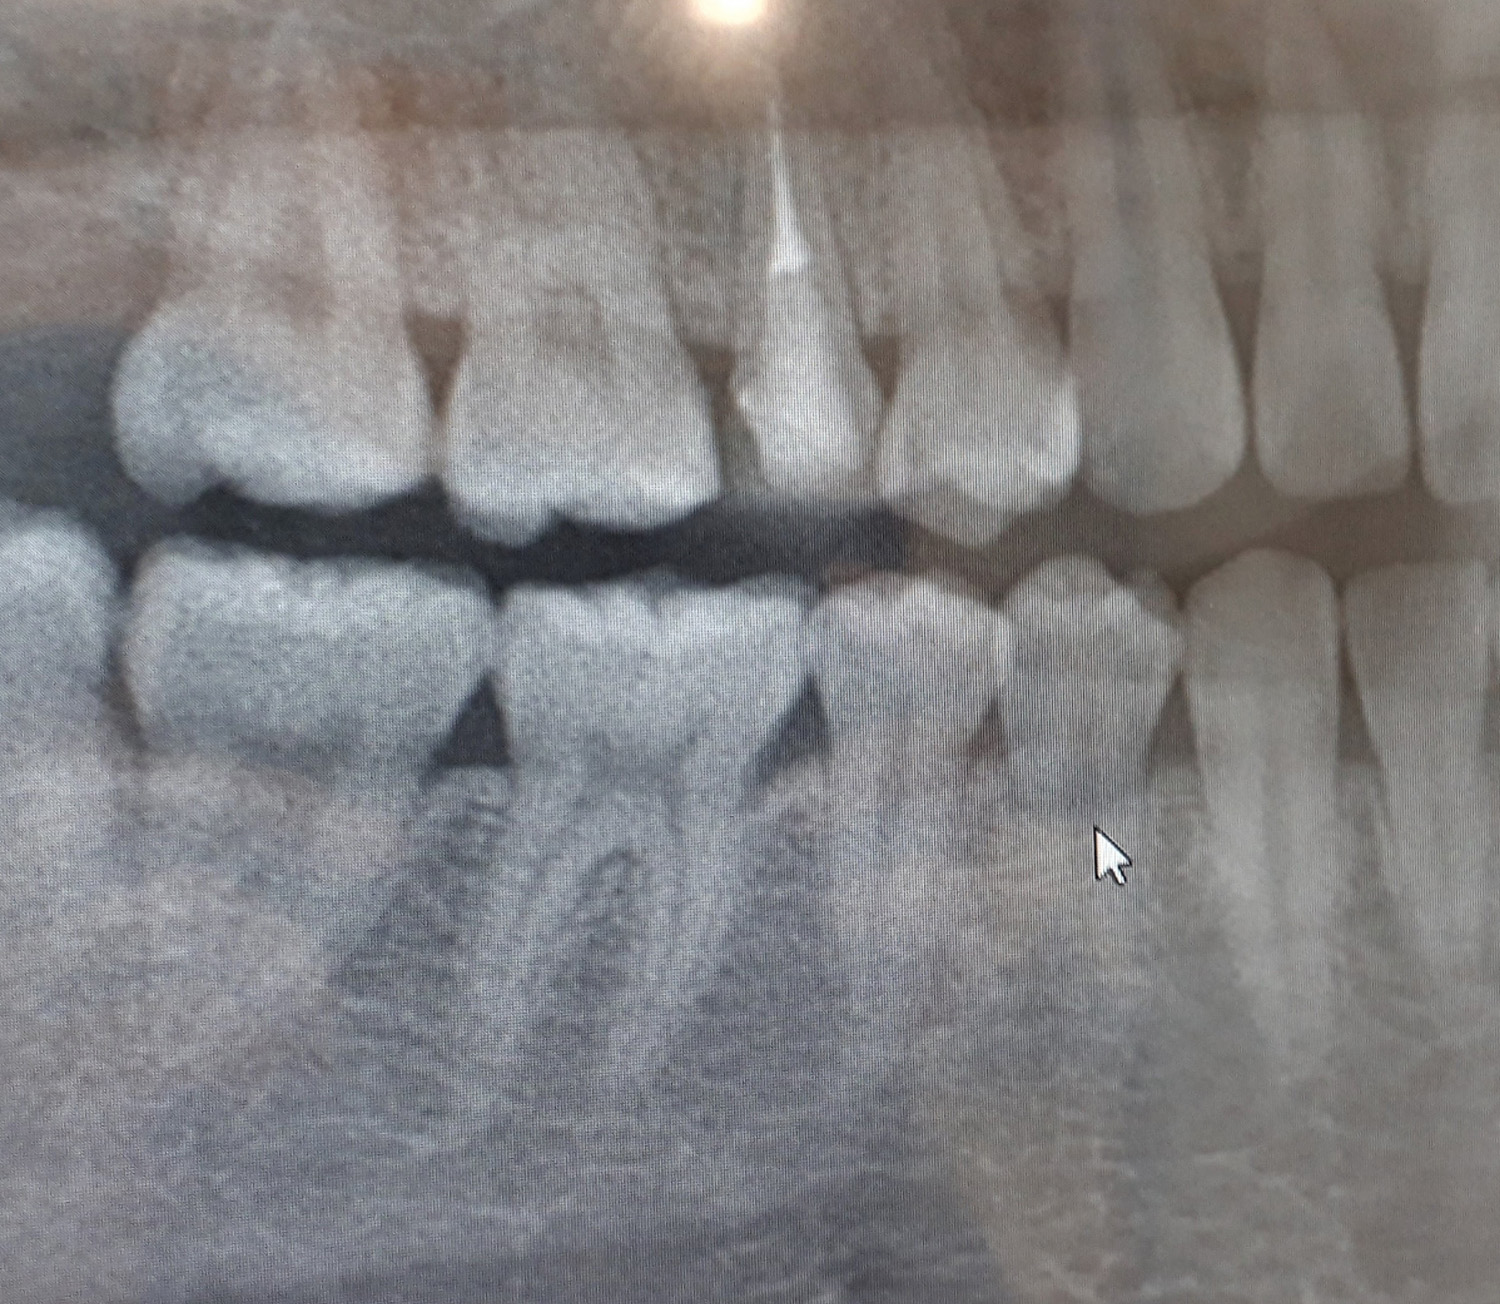

歯を失う主な原因は、むし歯による歯へのダメージや歯の神経(歯髄)が病気になる歯根の病気、歯周病などにより歯の土台」が崩れてしまうことが挙げられます。

上記のような状態を防ぐために、保存歯科の治療方法としては、「むし歯の治療」「歯内治療」「歯周病治療」の3つを専門的に行います。